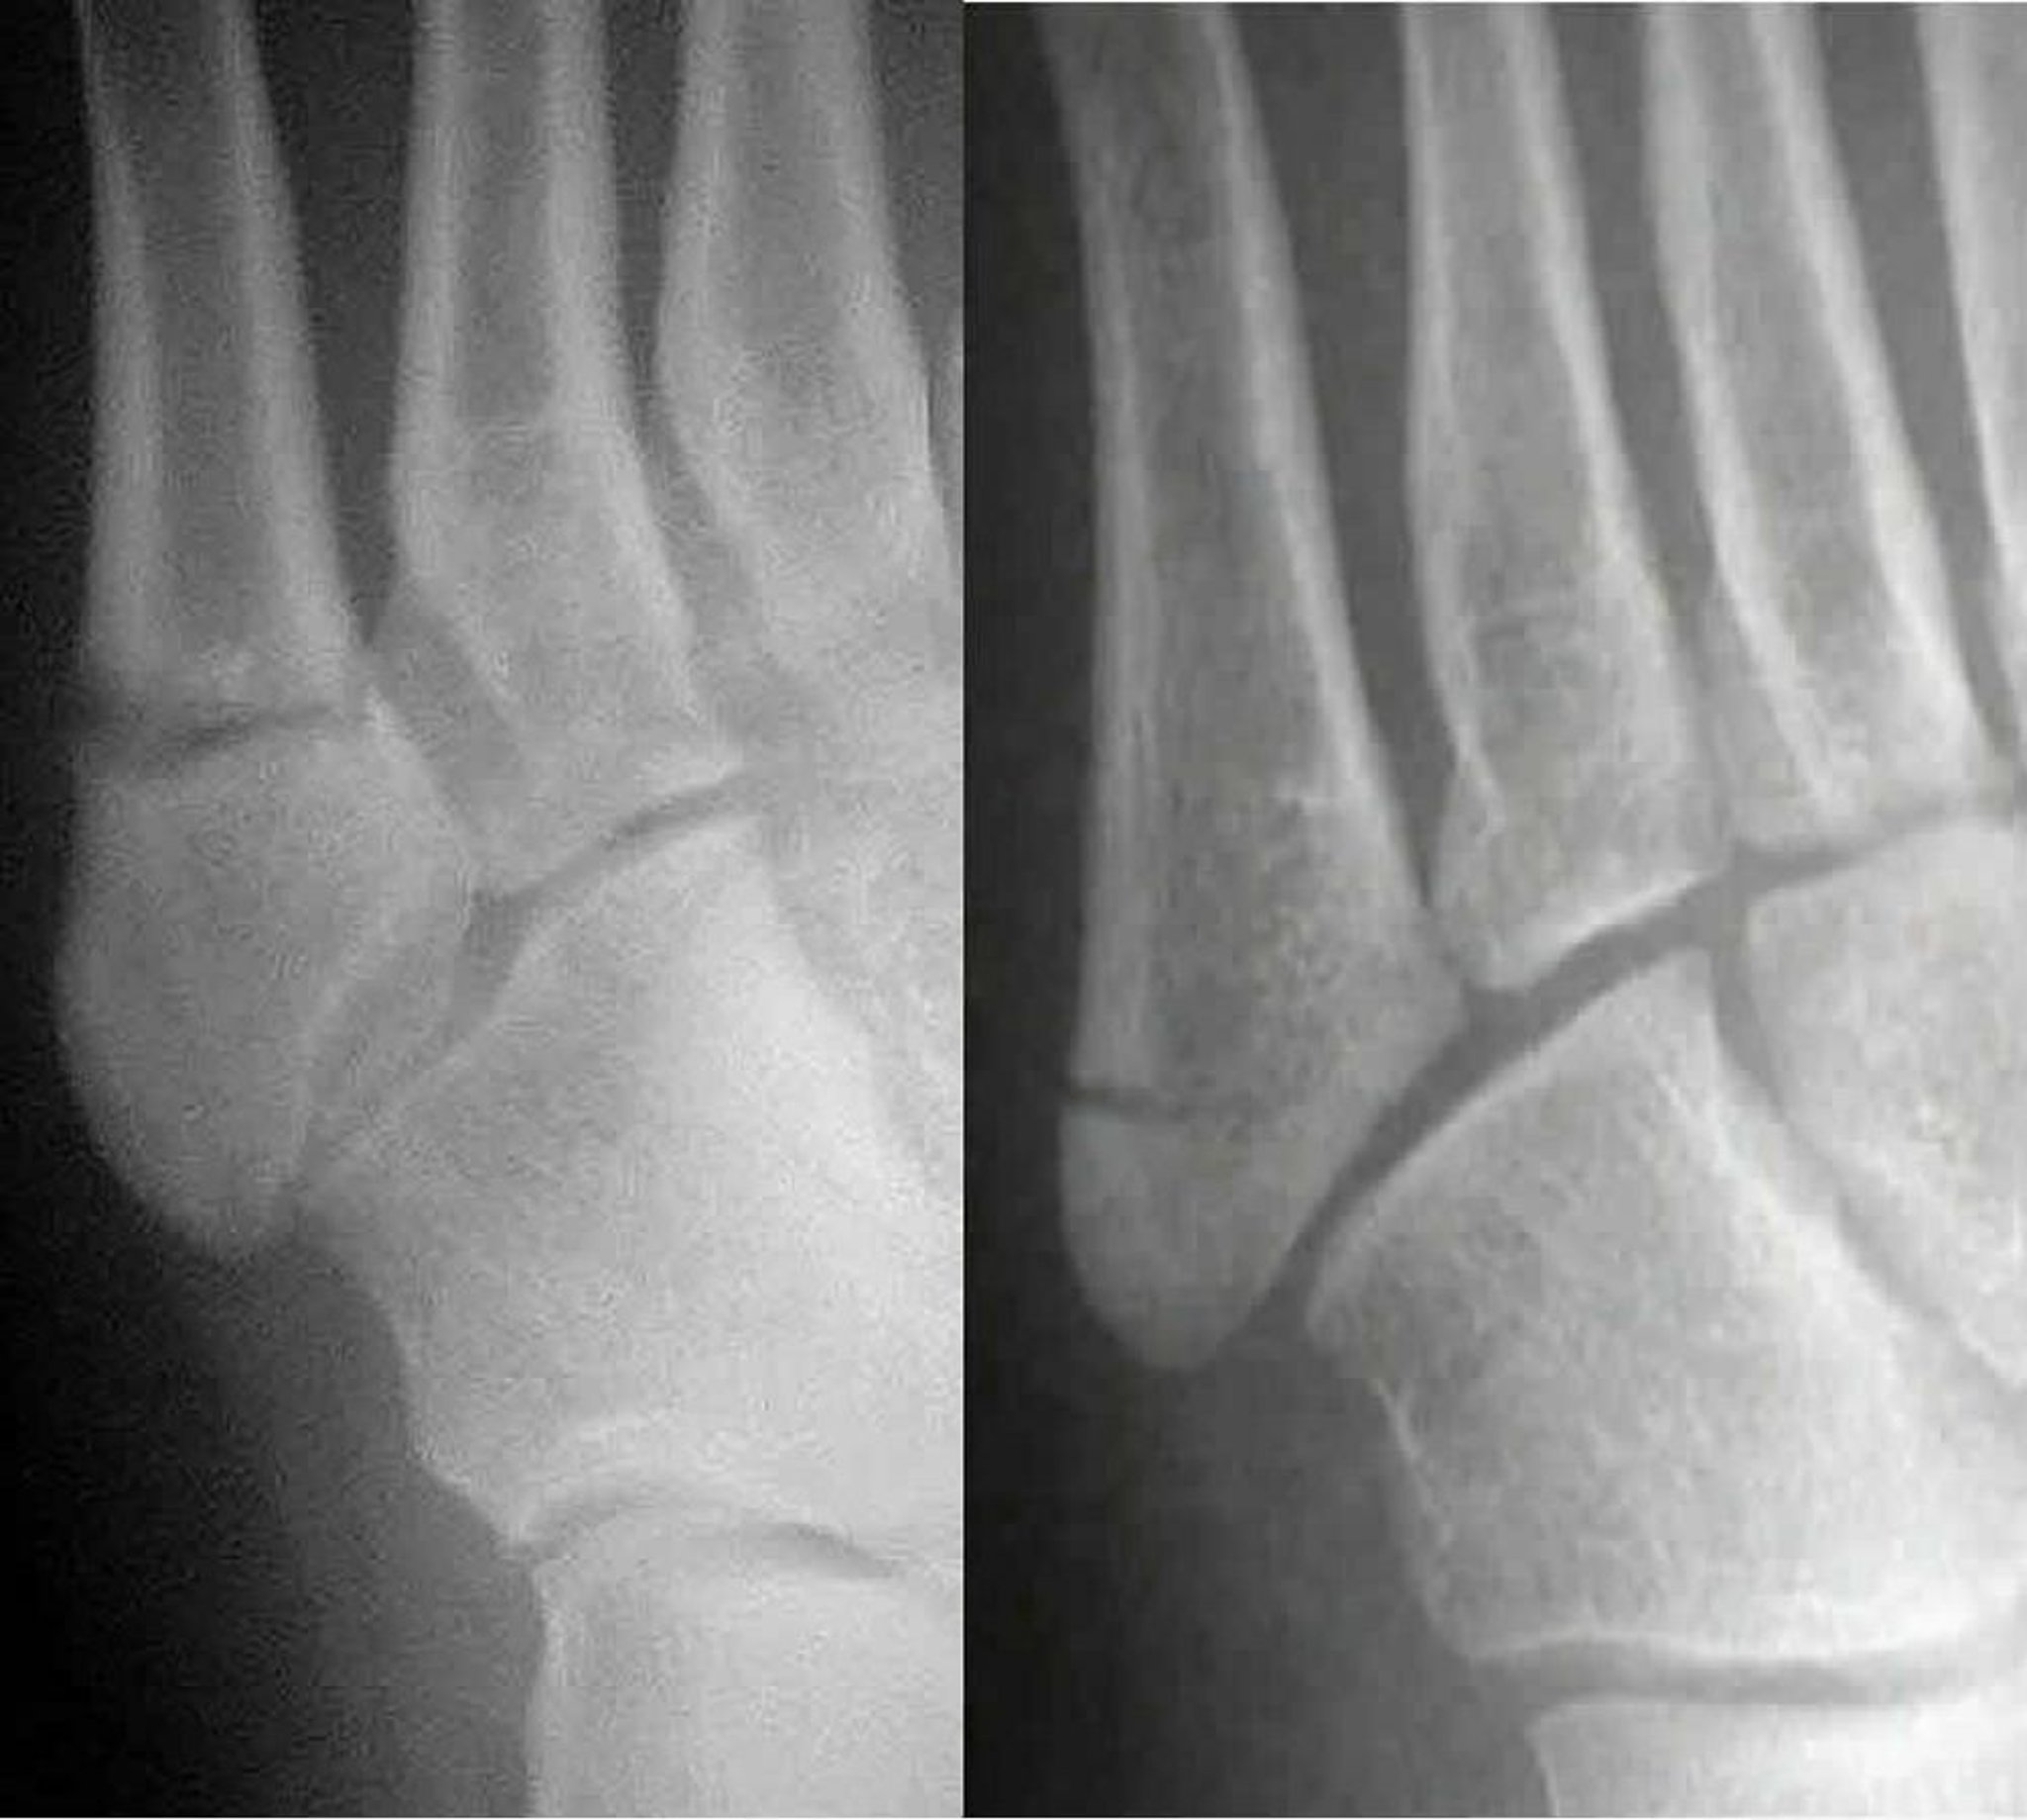

Fracturas de Jones comparadas con seudofracturas de Jones

Una fractura de Jones (izquierda) compromete el eje del quinto metatarsiano; una fractura de seudo-Jones (derecha) involucra la base del quinto metatarsiano. La distinción entre las dos es importante debido a que se tratan de modo diferente.

Images courtesy of Danielle Campagne, MD.